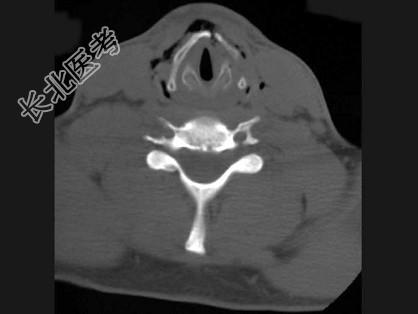

- 多项选择题男,27岁, 开车外出在高速行驶时翻车,呼吸困难, 喉部肿胀,CT检查如图所示, 正确的描述或诊断是 ( )

A、左侧甲状软骨骨折

B、左侧梨状窝软组织肿胀

C、颈部、胸骨下方软组织积气

D、左侧杓状软骨骨折

E、考虑喉、气管破裂